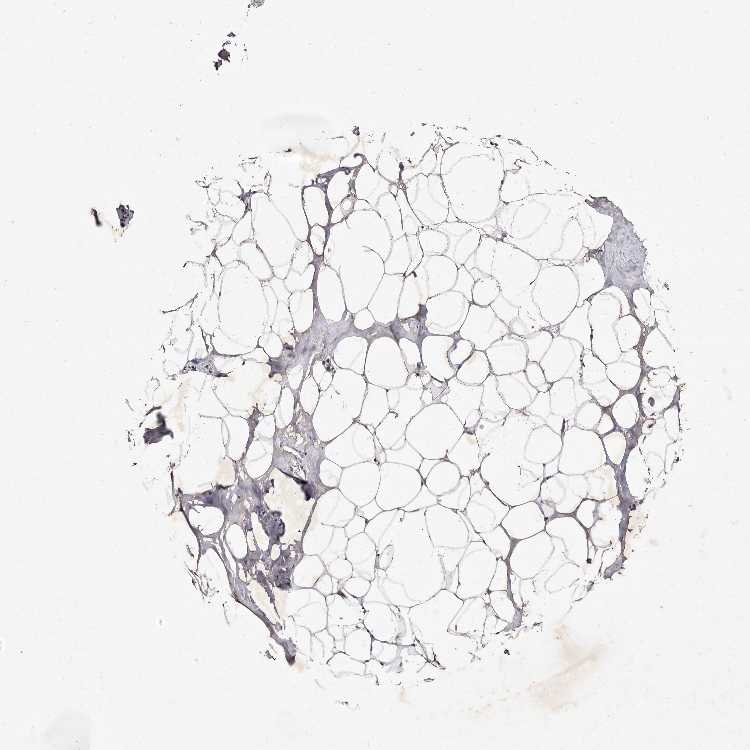

ADIPOSE TISSUE - Antibody stainingi

Antibody staining in the annotated cell types in the current human tissue is reported as not detected, low, medium, or high, based on conventional immunohistochemistry profiling in selected tissues. This score is based on the combination of the staining intensity and fraction of stained cells.

Each image is clickable and will lead to virtual microscopy that enables deeper exploration of all samples and also displays staining intensity scores, fraction scores and subcellular localization as well as patient and tissue information for each sample.

Antibody HPA025690

Adipocytes Low